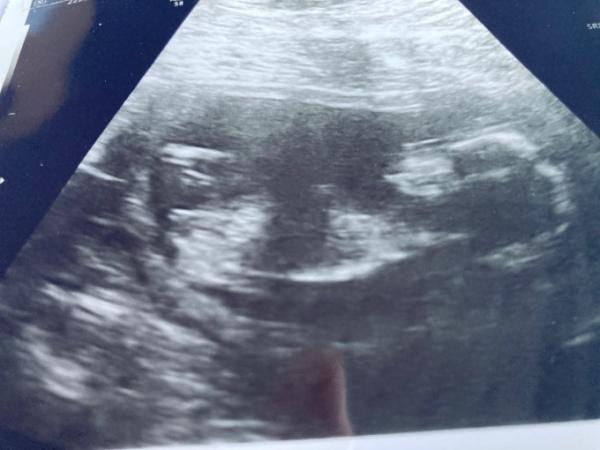

Hallihallo ihr Lieben, Heute war mein 3. Ultraschall und wir werden erst das Geschlecht erfahren beim Geburt. Das Baby petzt immer die Beine zusammen beim US. Hier mal ein Bild von 15+0 da hat die FA nicht gesagt was es wird. Deutlicher wird es einfach überhaupt nicht Wer möchte, sag einfach was du denkst . LG Rosi

Bild zu Geschlecht erraten - Schwanger - wer noch? Rund um die Schwangerschaft

Hallo Also ich finde hier ist einfach unmöglich was zu sehen

Hi Laut Nub ist es ein Mädchen Lg